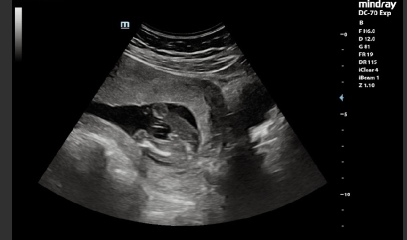

I went for a gender scan at 17 weeks and was told baby was a boy. This sonographer was confident and shared photos of baby boy.

I’ll add photos of my 17 week scan that confirmed baby was male. I’ve booked a rescan so will find out then, just curious!

I went for another private scan and they were 100% convinced that baby is a boy.

I’ve been for a 4D scan since and it’s pretty clear.